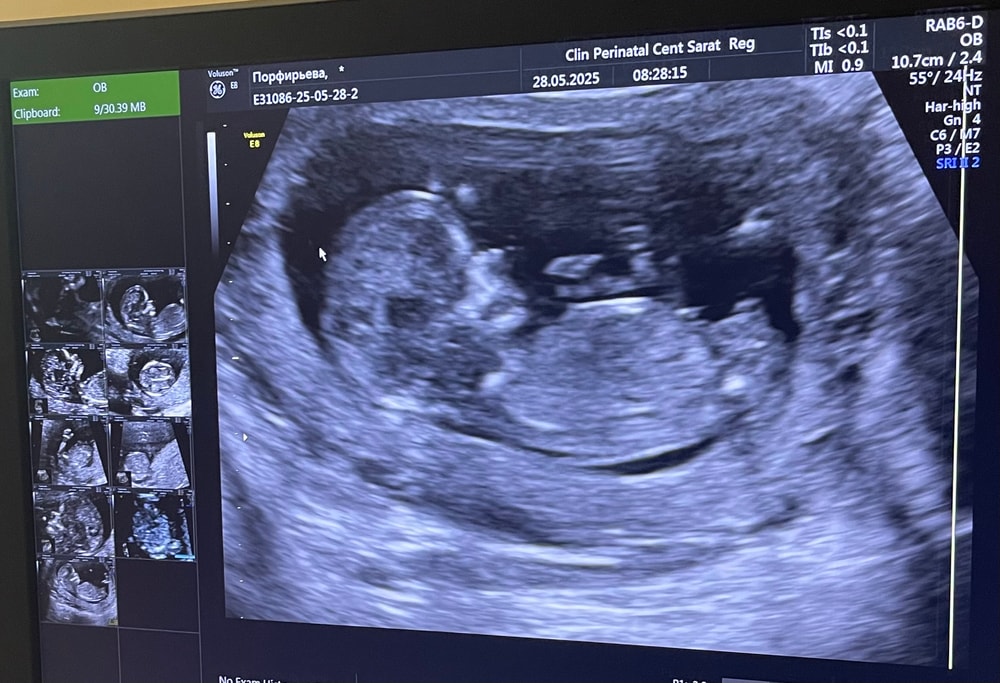

Лена в Благополучная беременность 6 месяцев Видно пол? Анализы, скрининги Девочки кто разбирается?! Видно пол? Сама не понимаю не вижу) Посмотрите еще 20 записей на эту тему Лучший ответ Светлана Нет, ножкой прикрыто 28.05.2025 Ответить Лена Светлана, спасибо) 28.05.2025 Ответить Отменить Ответить Nika Думаю, что мальчик 28.05.2025 Ответить Лена Nika, спасибо)) 28.05.2025 Ответить Юлия Мальчуган 🤞😎 28.05.2025 Ответить Лена Юлия, спасибо) 29.05.2025 Ответить Юлия Лена, напишите потом, как узнаете кто😇 29.05.2025 Ответить Лена Юлия, ок) 30.05.2025 Ответить Оливия 28.05.2025 Ответить Оливия Ол, все, что нужно знать про пол в 12-13 недель))) 28.05.2025 Ответить Лена Ол,скажите кого вы видите? Я честно нифига не пойму даже по углу ) 28.05.2025 Ответить Оливия Лена, лялю вижу))) а вообще пол определять на этом сроке тот еще аттракцион😂😂😂 28.05.2025 Ответить Лена Ол, точно😁главное здоровый чтобы был 28.05.2025 Ответить Лена У меня мальчик!!!👦 24.07.2025 Ответить Результаты анализов 1 скрининг Чаты Беременных Выберите чат: Январята-2026 Февралята-2026 Мартята-2026 Апрелята-2026 Майчата-2026 Июнята-2026 Июлята-2026 Августята-2026